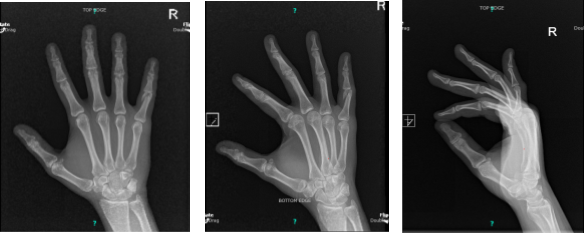

X-ray Right hand minimum 3 years